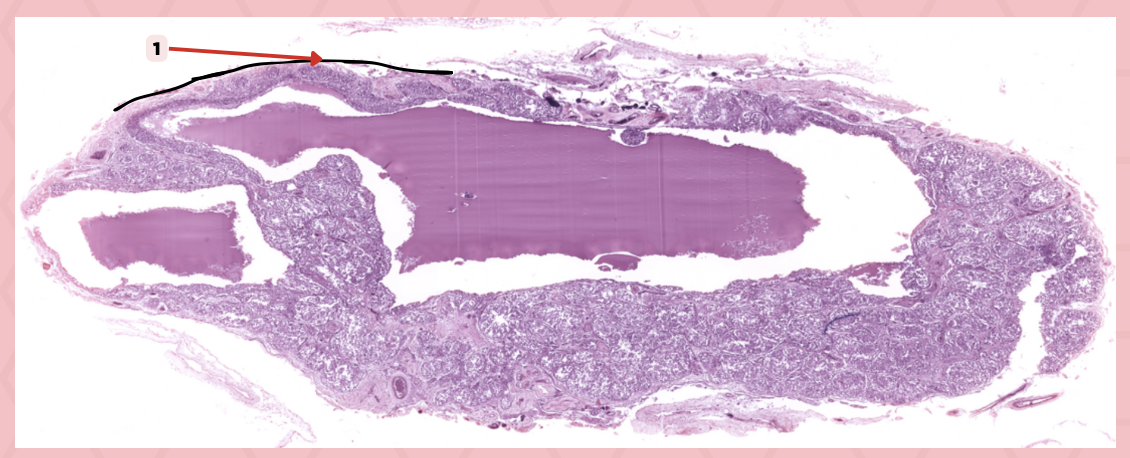

Thyroid-Parathyroid

Identify the specimen.

Thyroid Gland

Identify the structure labeled as 1.

Capsule

Identify the structure labeled as 2 and 4.

Parathyroid Gland

Identify the structure labeled as 3.